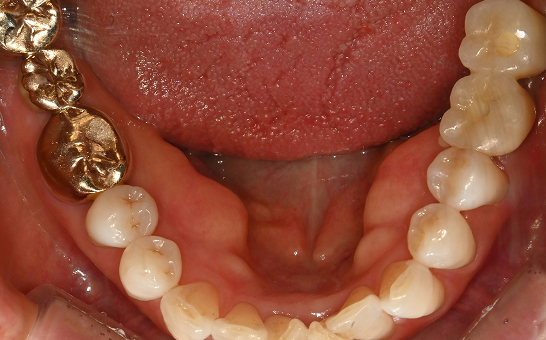

CASE 05 하** / 50대

임플란트 재수술

치료 시작 전 촬영 2024.06.05 | 치료 완료 후 촬영 2025.01.04

1 실패한 임플란트 제거

2 뼈이식 후 재식립

3 건강한 잇몸 유지 중